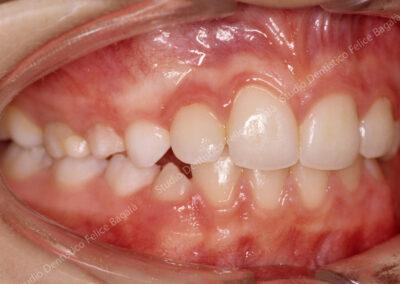

IL CASO DI DANIELE (MORSO CROCIATO)

Daniele 8 anni Morso crociato destro con deviazione mandibolare  e linee mediane dallo stesso lato (vedi frecce nere). Dopo allargamento della parte superiore (mascellare e palato) la mandibola si porta al centro (vedi frecce nere) . Daniele da quel momento continuerà a crescere e sarà controllato periodicamente. Dopo questo breve fase intercettiva di durata di 8/10 mesi non ha avuto più alcun bisogno di ortodonzia. Le deviazioni mandibolari da morso crociato vengono annoverate tra i principali motivi di disturbi muscolo articolari ( Disfunzioni ATM) nell’adulto.

Prima